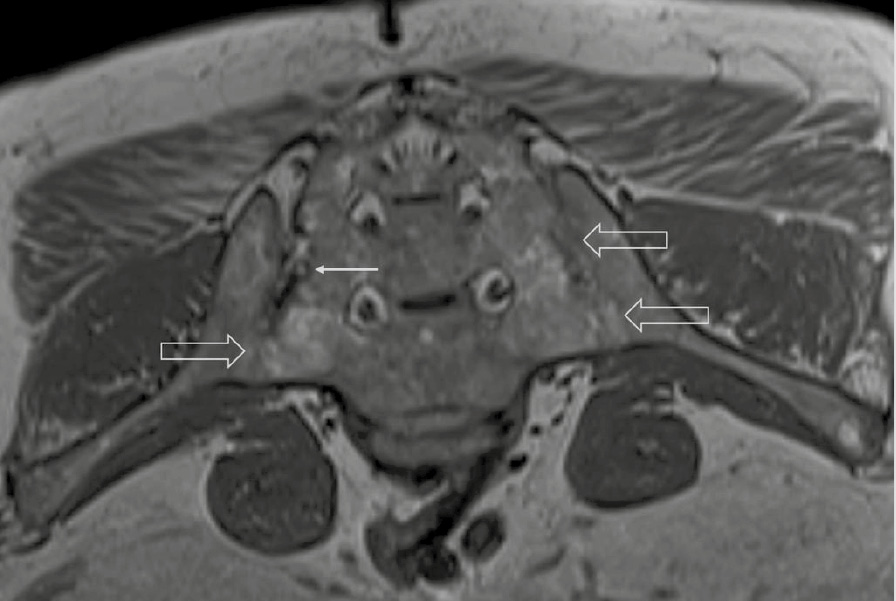

При компьютерной томографии органов грудной клетки данных за «свежие» очаговые и инфильтративные изменения не получено. Увеличения лимфатических узлов подмышечных областей, средостения, корней легких не выявлено. Отмечался усиленный грудной кифоз, обызвествление передней продольной связки, на всем уровне исследования определялись передне-боковые спондилофиты, а также анкилоз большинства реберно-поперечных суставов. По данным рентгенографии кистей (рис. 1, 2) и стоп (рис. 3, 4) диагностированы признаки эрозивного артрита, анкилоз суставов запястья. По данным МРТ крестцово-подвздошных суставов (КПС) определялся неравномерный анкилоз КПС, хрящи по суставным поверхностям неравномерной толщины, примерно на половине протяжении сустава отсутствуют, «суставной промежуток» облитерирован. Неравномерность и нечеткость контура суставных поверхностей за счет множества краевых эрозий справа, единичных – слева, с наличием остеокластоза, в нижнем отделе слева по смежным отделам определяются участки трабекулярного отека, данная находка клинически интерпретирована как двусторонний активный сакроилиит (рис. 5, 6).

Рис. 5. Магнитно-резонансная томография (Т2-взвешенное изображение в поперечной проекции). Протяженные участки анкилоза крестцово-подвздошных сочленений (толстые стрелки), эрозии суставных поверхностей (тонкие стрелки)

Ведущим диагнозом в течение всей истории заболевания был «анкилозирующий спондилоартрит, смешанная форма, HLA-B27-ассоциированный», поставленный на основании типичного поражения позвоночника с формированием деформаций (костный анкилоз в переднем отделе Th4 и Th7, множественные синдесмофиты в области передних углов тел позвонков). Заключение МРТ КПС типично для пациента с АС: двусторонний анкилоз КПС, множественные краевые эрозии, с наличием остеокластоза и признаками трабекулярного отека костной ткани, двусторонний сакроилиит. Клиническая картина, проявляющаяся болями воспалительного характера и скованностью в пояснично-крестцовом отделе позвоночника, нарушением объема движения в позвоночнике, была характерна для прогрессирования АС. Диагноз подтверждался наличием положительного гена HLA-B27 [2].